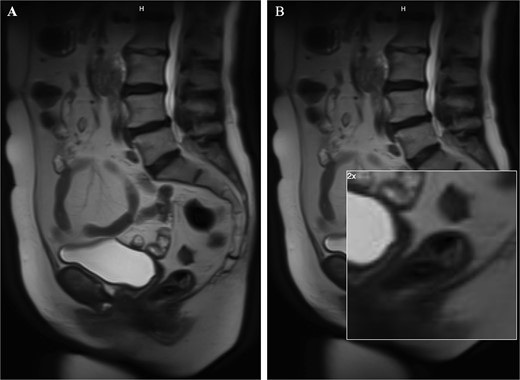

A 62-year-old woman with a past medical history of well-controlled type two diabetes, hypothyroidism, and chronic obstructive pulmonary disorder presented with several years of watery diarrhea. She denied abdominal pain, nausea, vomiting, hematochezia, melena, or weight loss. Her physical exam was unremarkable. Laboratory workup was within normal limits. She had not had a screening colonoscopy in the past. She underwent a colonoscopy, which revealed a 60 mm partially obstructing rectal polyp (Fig. 1A). Pathology from initial biopsies confirmed tubulovillous adenoma without dysplasia. The decision was made to proceed with flexible sigmoidoscopy and endoscopic resection. The lesion involved the distal rectal fold and was quite large, making ESD difficult. A decision was therefore made to proceed with EMR. This was successful in removing ~70% of the lesion; however, the central area appeared scarred, and there was concern for deeper submucosal involvement preventing complete resection. This could not be removed with full-thickness resection, cold snare piecemeal resection, or hot snare polypectomy despite further attempts at lifting, ~25 mm of the polyp (the central portion) remained (Fig. 1B); therefore, the patient was referred to colorectal surgery for further evaluation and to attempt completion TEMS. Repeat biopsies at the central residual portions of the polyp revealed tubulovillous adenoma with focal high-grade dysplasia without invasive carcinoma. An MRI of the abdomen and pelvis with contrast was performed several weeks later to evaluate for metastatic disease or deep rectal invasion. Imaging demonstrated a small polypoid enhancing mass within the posterior wall of the left mid-rectum that measured 2.2 × 1.2 cm, without invasion of the muscularis propria (Fig. 2A and B). There were no findings concerning for malignancy or metastatic disease. Decision was made to proceed with TEMS to complete the resection, in hopes of an organ-preserving intervention. She ultimately underwent trans-anal excision of the remaining 25 mm polyp several months later with colorectal surgery. This procedure was uncomplicated. Final pathology showed a 20 mm tubulovillous adenoma, which was completely excised with negative margins and without evidence of residual high-grade dysplasia. At follow-up of 4 months later, the patient reported resolution of her diarrhea. At the 6-month follow-up, flexible sigmoidoscopy revealed a large scar in the rectum without recurrent or residual polypoid tissue (Fig. 3A and B). Biopsies obtained from the scar site confirmed no recurrence.

Images from the MRI abdomen pelvis with contrast. This depicts a small polypoid enhancing 2.2 cm mass within the posterior wall of the left mid rectum without invasion of the muscularis propria. The image on the right is a zoomed in image of the remaining polyp.